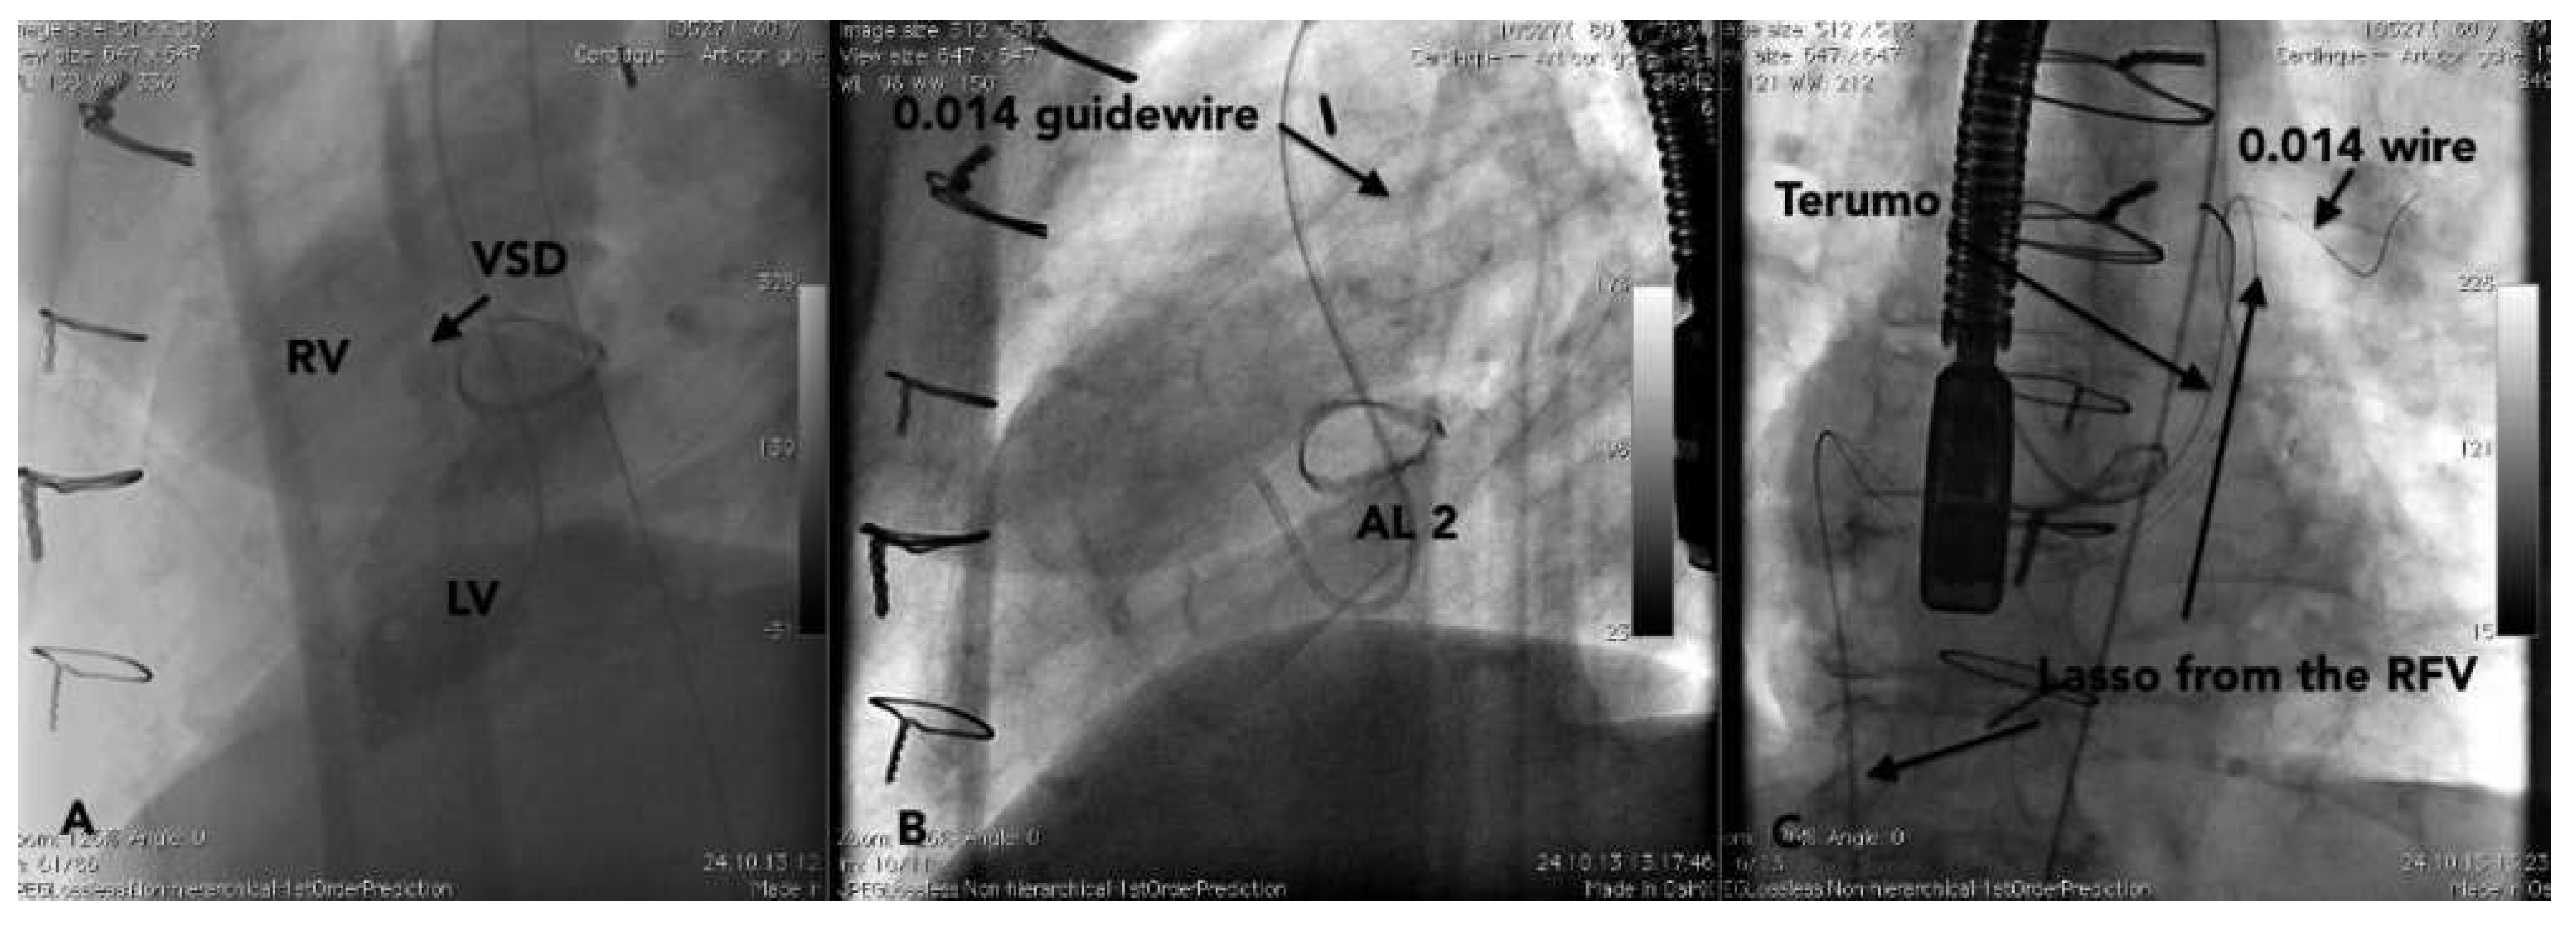

Case report